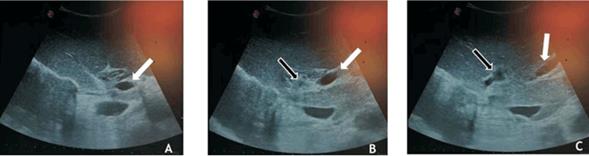

A las cinco semanas se evidenció por tomografía oclusión del origen de la vena porta derecha, la cual se encontraba repermeabilizada a nivel intrahepático (figura 2). El volumen hepático total (VHT) era de 1.408 cm3 y el volumen del FHR de 663,8 cm3, con un cociente FHR/ VHT de 47%, representando un crecimiento de 20% respecto al volumen inicial, por lo que a las siete semanas de la primera hepatectomía se procedió a la hepatectomía derecha. Se realizó ecografía intraoperatoria confirmando la oclusión del origen de la vena porta derecha, con repermeabilización intrahepática de ésta (figura 3). Se completó la cirugía propuesta sin incidentes. Buena evolución posoperatoria, sin elementos de FHPO.

Figura 3: Ecografía de abdomen intraoperatoria, corte longitudinal a nivel del hilio hepático. A) Tronco de la vena porta (flecha). B) Sitio de bifurcación portal. Vena porta izquierda (flecha blanca). Se evidencia sitio de ligadura portal derecha (flecha negra). C) Ramas intrahepáticas de vena porta izquierda (flecha blanca) y ramas intrahepáticas de la vena porta derecha repermeabilizadas (flecha negra).

Si bien en nuestro paciente no se evidenció directamente la presencia de ramas colaterales entre ambos lóbulos hepáticos, en la tomografía de control se visualizó la rama portal derecha intrahepática permeable, lo cual fue confirmado mediante ecografía intraoperatoria, sugerente de dicha colateralidad. Sin embargo, el VHR fue adecuado y pudo completarse la hepatectomía.